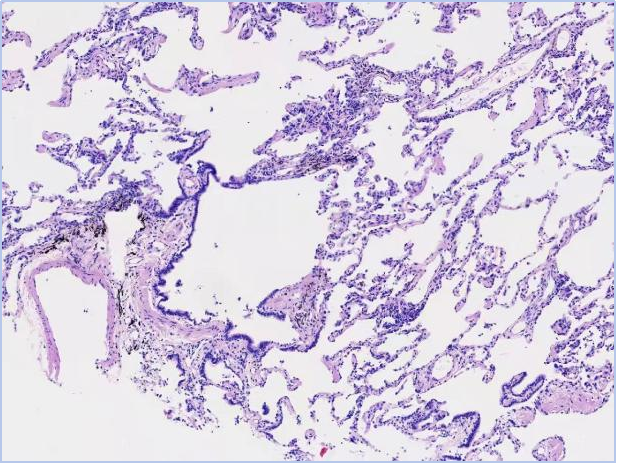

△患者肺活检标本,可见明显的肺泡结构,肺泡间隔增宽。